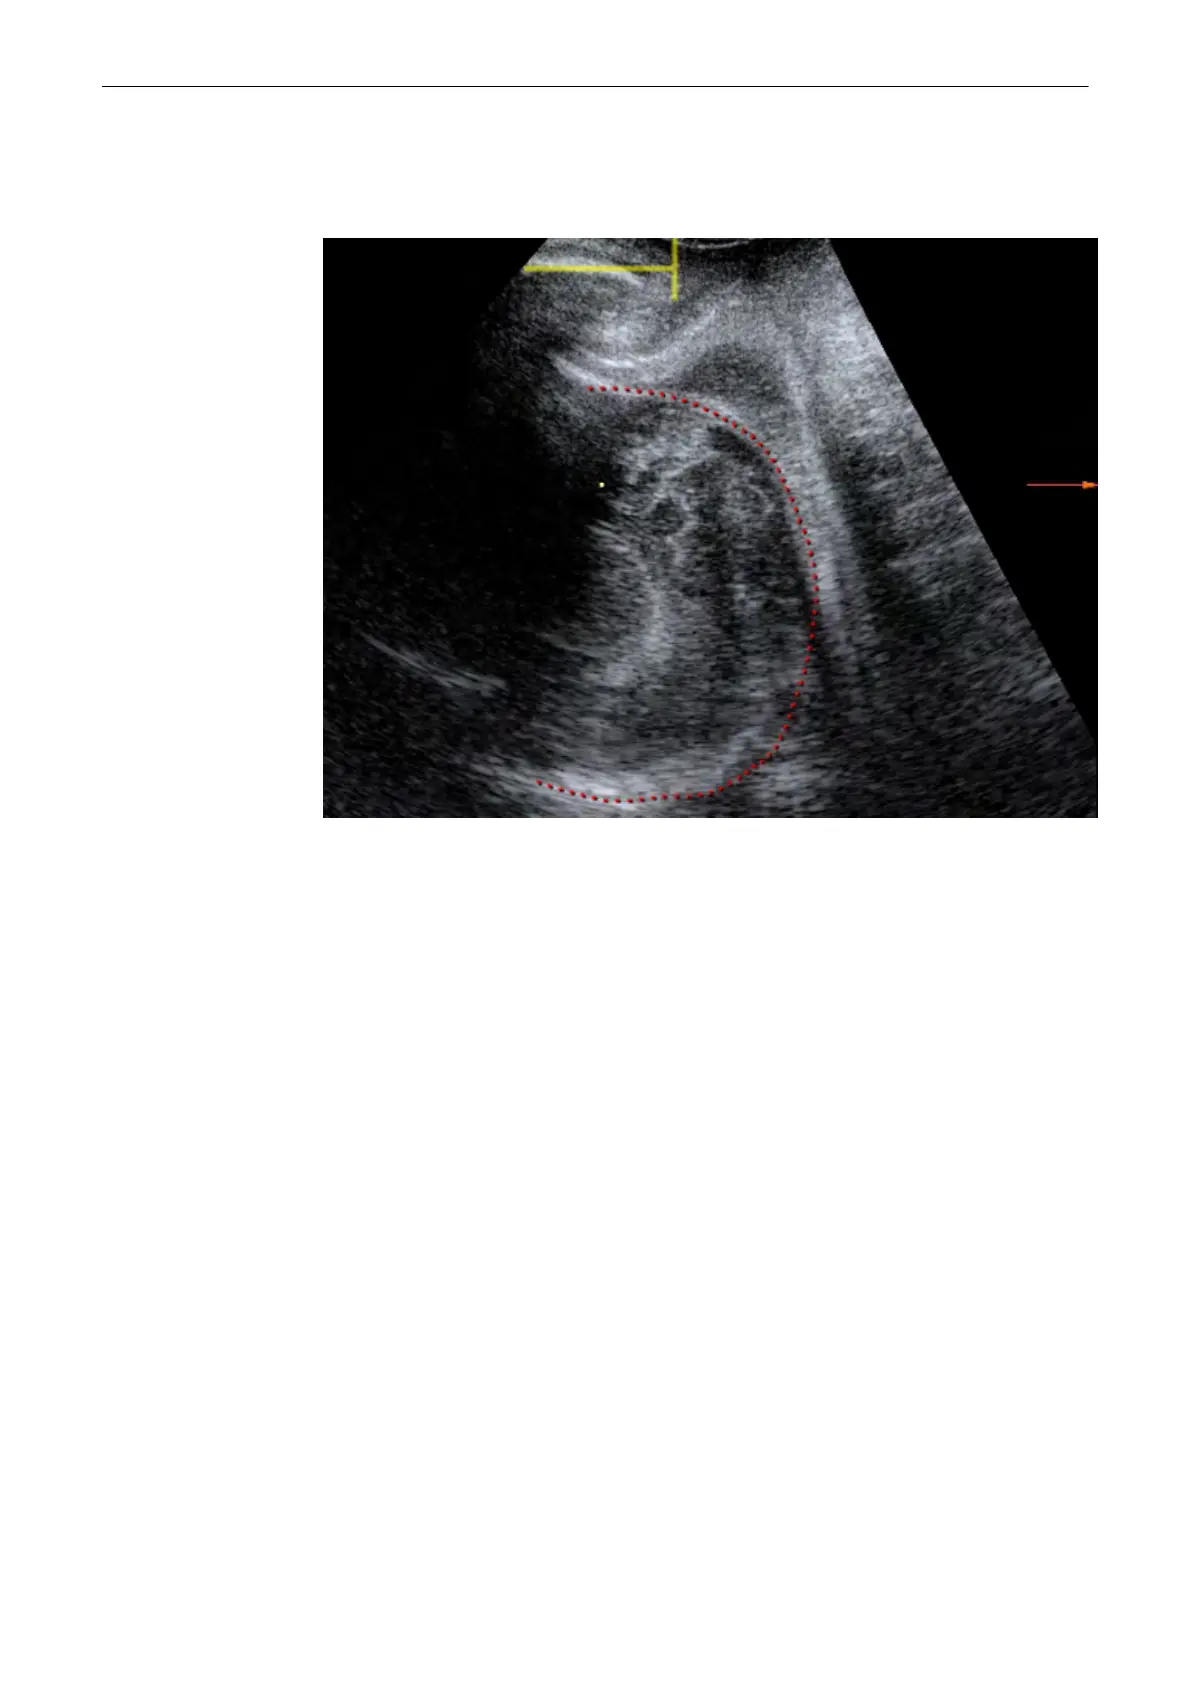

9.15.4 Set fetal contour

Trace the position of the fetal head point by point.

9.15.5 Set head direction

Draw a line of two points along the maximum head diameter. Then mark the most distant point

of the head contour. The head direction is automatically calculated as a line orthogonal to the